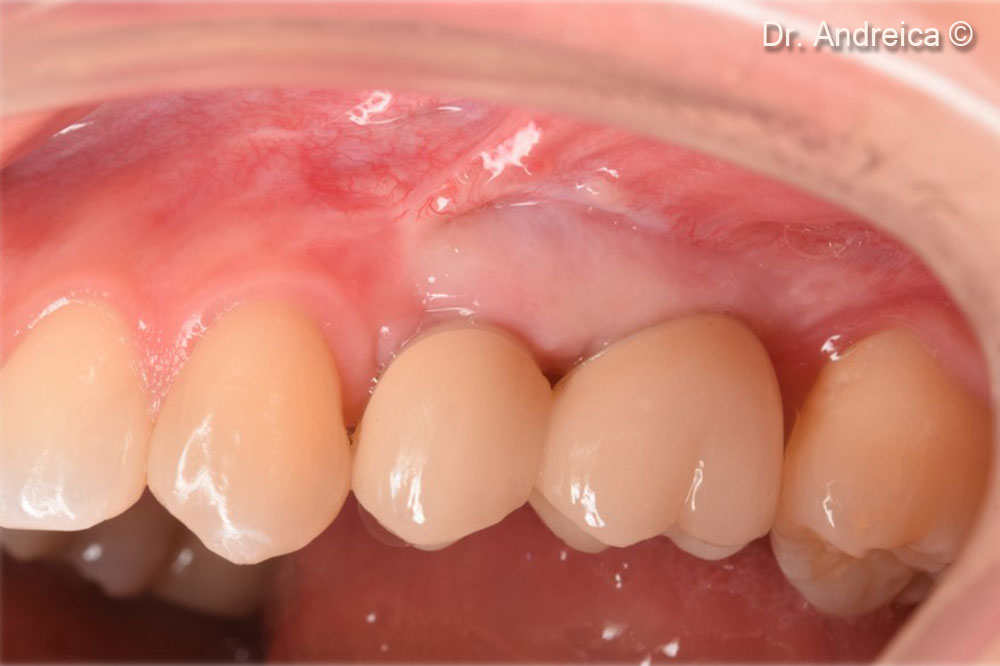

Buccal view of the posterior left maxilla showing a lack of the vestibule and a mucogingival line displaced palatally